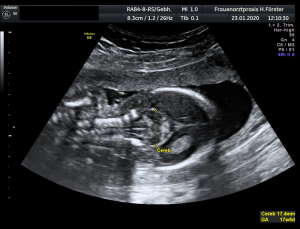

Gynäkologische Grundversorgung Frauenärztliche Krebsfrüherkennungsuntersuchung Nachsorge und supportive Therapie bei bösartigen gynäkologischen Tumoren Impfungen Brustultraschall Ultraschalluntersuchung der weiblichen Genitalorgane Psychosomatische Grundversorgung Chlamydienscreening FOB-Test (früher Hämoccult) Kontrazeption Geburtshilfliche Grundversorgung Geburtshilflicher Basisultraschall Erweiterter Basisultraschall (Organscreening) zw, 18-22.SSW Doppler/Duplexsonografie des fetomaternalen Gefäßsystems Infektionsscreening in der Schwangerschaft CTG (Kardiotokographie) Gynäkologische Grundversorgung Dies umfasst die Abklärung und Behandlung gynäkologischer Erkrankungen. Eine große Rolle dabei spielt das ärztliche Gespräch, ergänzt bei Notwendigkeit durch die gynäkologische Untersuchung oder Untersuchung der weiblichen Brust. In vielen Fällen werden noch Zusatzuntersuchungen durchgeführt (z.B. Ultraschalluntersuchungen, Abstrichentnahmen, Blutentnahmen) oder weiterführende Untersuchungen veranlasst (z.B. Röntgenuntersuchungen). >> zurück << Frauenärztliche Krebsfrüherkennungsuntersuchung Die Krebsfrüherkennungsuntersuchung der Frau ist wahrscheinlich die bekannteste Leistung unseres Fachgebietes. Ab dem Alter von 20Jahren hat jede Frau ein Anrecht auf diese jährliche Untersuchung. Dabei werden der Unterleib der Frau und ab dem Alter von 30Jahren auch die Brüste der Frau systematisch klinisch untersucht. Zusätzlich erfolgte seit vielen Jahren ein Pap-Abstrich vom Gebärmutterhals. So konnten Zellveränderungen meist rechtzeitig erkannt und behandelt werden und es wurde erreicht, daß das früher sehr häufige Zervixkarzinom (Gebärmutterhalskrebs) heute nur noch selten auftritt. Um die Qualität weiter zu verbessern erfolgte 2020 eine Neuordnung des Screenings mit Überarbeitung der Abstrichintervalle und Hinzunahme von HPV-Abstrichen ab 35 als Kassenleistung. >> zurück << Nachsorge und supportive Therapie bei bösartigen gynäkologischen Tumoren Nach Abschluss und oft auch wärend der Primärbehandlung können Probleme auftreten. Es macht also Sinn, sich in regelmäßigen Abständen zu treffen, um das weitere Vorgehen zu planen, eventuell Zusatzuntersuchungen zu veranlassen oder zusätzlich wegen der Beschwerden zu behandeln. Die Nachsorgeuntersuchungen finden anfangs engmaschig statt, später werden die Intervalle länger. >> zurück << Impfungen In Zeiten der Globalisierung, zunehmender Reisefreudigkeit und Zuwanderung werden wir wieder mit Infektionserregern konfrontiert, die wir schon als besiegt geglaubt hatten. Gleichzeitig werden wir immer älter und unser Immunsystem dabei nicht besser. Es reicht nicht, mal eben alle 10Jahre Tetanus zu impfen. Sind Sie geschützt? Wissen Sie was empfohlen ist? Bringen Sie den Impfausweis (auch den alten!!) mit. Wir prüfen Ihren Impfstatus, geben Ihnen Empfehlungen. Die gängigsten Impfstoffe haben wir auch vorrätig und können Sie impfen. >> zurück << Brustultraschall Die Ultraschalluntersuchung der Brust (Mammasonografie) kommt zur Abklärung von krankhaften Veränderungen zur Anwendung oder als Zusatzuntersuchung in der Früherkennung von Brustkrebs bei sehr dichtem Gewebe oder familiärer Vorbelastung. Sie ersetzt nicht das organisierte Mammographiescreening und ist nicht Bestandteil der normalen Krebsfrüherkennung. Es handelt sich um eine schmerzfreie Untersuchung ohne Strahlenbelastung. Die Mammasonografie  ist auch als Wunschleistung (IGeL) möglich. >> zurück << Ultraschalluntersuchung der weiblichen Genitalorgane Die Ultraschalluntersuchung der weiblichen Genitalorgane kommt zur Abklärung von krankhaften Veränderungen des weiblichen Genitales zur Anwendung. Dabei werden mit einer hochfrequenten Vaginalsonde die Organstrukturen im kleinen Becken untersucht. Die Untersuchung ist bei schlanken und sehr jungen Frauen auch vom Bauch aus möglich, die Genauigkeit ist dabei technisch bedingt aber schlechter.  Sie ist nicht Bestandteil der normalen Krebsfrüherkennung. Auch diese Untersuchung ist als Wunschleistung (IGeL) möglich. >> zurück << Psychosomatische Grundversorgung Jede Erkrankung belastet die Seele. Eine seelische Belastung macht den Körper krank. Jeder weiß das. Die Zusammenhänge zwischen dem kranken Körper und der kranken Seele beschreibt die Psychosomatik. Ein "Gordischer Knoten", der nur schwer zu zerschlagen ist, oft ein langer Weg. Ziel ist es, diese Zusammenhänge zu erkennen und den Betroffenen zu helfen ihren Weg zu finden. Oft ist die Zusammenarbeit mit einer Psychologin/ Psychologen nötig. Wichtig ist die Hilfe bei den ersten Schritten. Laufen müssen Sie selbst. >> zurück << Chlamydienscreening Das Bakterium Chlamydia trachomatis kann beim Sex übertragen werden und zu Entzündungen und sogar zur Unfruchtbarkeit führen. Deshalb bezahlen die Krankenkassen bis zum vollendeten 25.Lebensjahr allen sexuell aktiven Frauen einen Suchtest auf Chlamydien. Sie müssen lediglich eine Urinprobe abgeben. Auch in jeder Schwangerschaft wird nach Chlamydien gefahndet. Da Frauen im Normalfall auch im Alter über 25Jahren sexuell aktiv sind und noch schwanger werden wollen bieten wir die Testung auch als Wunschleistung (IGeL) an. Der Test wird dann aus einem Abstrich aus dem Muttermund entnommen, dies kann bei der Krebsfrüherkennung mit gemacht werden. >> zurück << FOB-Test (früher Hämoccult) Im Alter von 50 bis 54Jahren bezahlen die Krankenkassen allen versicherten Frauen einen Stuhltest zur Früherkennung von Darmkrebs oder seiner Vorstufen. Mit 55Jahren können Sie sich entscheiden zwischen zwei Darmspiegelungen im Abstand von 10Jahren oder der Fortführung der Stuhlteste alle 2Jahre. Natürlich kann man Stuhlteste auch zwischen den Darmspiegelungen machen lassen oder auch bei Frauen jünger als 50. Wir bieten dies als Wunschleistung (IGeL) unseren Patienten an. >> zurück << Kontrazeption Ein selbstbestimmtes Leben als Frau ist bei uns in Deutschland eine Selbstverständigkeit. Das war nicht immer so.  Kinder-Küche-Kirche hieß es früher, damals, in der guten alten Zeit. Das ist zum Glück vorbei. Und begonnen hat alles mit der Pille. Frauen konnten endlich über ihren Körper selbst bestimmen, ohne Angst ihre Liebe leben.  Aber die Pille ist nicht alles. Viele Märchen sind im Umlauf, Fehlinformation. Aber auch fehlendes Wissen zu Risiken.  Wir beraten Sie gern. >> zurück << Geburtshilfliche Grundversorgung In der Schwangerenberatung werden die werdenden Muttis gemäß den geltenden Mutterschaftsrichtlinien vom Anfang der Schwangerschaft bis zur Abschlussuntersuchung (6-8 Wochen nach der Geburt) betreut. >> zurück << Geburtshilflicher Basisultraschall Nach Vorgabe der Mutterschaftsrichtlinie sind sind in der Schwangerschaft 3 Ultraschalluntersuchungen vorgesehen. Diese finden in der 8.-12. SWW, in der 18,- 22. SSW und in der 28.-32.SSW statt. Dabei werden der Zustand des Embryos/ Feten, des Fruchtwassers und der Plazenta beurteilt. >> zurück << Erweiterter Basisultraschall (Organscreening) zw. 18-22.SSW Bei der zweiten Ultraschalluntersuchung (zw.18.-22. SSW) erfolgt ein erweitertes Screening mit Beurteilung der Organstrukturen des Kindes. Diese Untersuchung ist Kassenleistung, kann aber bei Wunsch auch Abgewählt werden, dann wird nur der Basisultraschall durchgeführt. >> zurück << Doppler/Duplexsonografie des fetomaternalen Gefäßsystems Bei Aüffälligkeiten im Schwangerschaftsverlauf oder auch bei bestimmten Vorerkrankungen oder Erkrankungen in einer früheren Schwangerschaft kann es notwendig sein die Durchblutung des Mutterkuchens und der Gefäße des Kindes zu Untersuchen. Hier kommt das Dopplerverfahren als Erweiterung des normalen geburtshilflichen Ultraschalls zum Einsatz. Dies erlaubt eine schnelle Zustandsbeurteilung des Kindes pepaart mit einer zeitlich begrenzten Vorhersage über die weitere wahrscheinliche Entwicklung. Bei entsprechender Indikation ist diese Untersuchung als Kassenleistung abrechenbar. >> zurück << Infektionsscreening in der Schwangerschaft Die Suche nach Krankheitserregern im Krankheitsfall ist Kassenleistung. Routinemäßig prüfen wir Ihren Schutz vor Röteln und Windpocken , in jeder Schwangerschaft erfolgt ein Test auf Chlamydien. Zusätzlich empfehlen wir jeder Schwangeren einen Test auf eine Besiedelung mit Gruppe-B-Streptokokken vor der Geburt. Diese Streptokokken können zu schweren Atemwegsinfektionen des Neugeborenen führen. Eine vorbeugende Behandlung bei positivem Test kann dann unter der Geburt erfolgen. Bei Wunsch kann auch ein erweitertes Erregerscreening über unser Labor erfolgen (Wunschleistung). Eine wichtige Rolle spielt auch die Kontrolle auf einen Schutz gegen eine Toxoplasmoseinfektion. Bei fehlendem Schutz empfielt sich die regelmäßige Testung aus dem Blut auf eine frische Infektion. Auch dies ist eine Privatleistung, wird aber von den meisten Kassen erstattet. Eine nicht erkannte und somit nicht behandelte Erstinfektion in der Schwangerschaft kann zu schweren Schäden beim Kind führen. >> zurück << CTG Ab etwa der 30.Schwangerschaftswoche können wir bei Notwendigkeit im Ramen der Schwangerschaftsvorsorge die kindlichen Herztöne (Kardiographie) und simultan dazu die die Spannung der mütterlichen Bauchdecke (Wehenschreiber, Tokographie) graphisch darstellen. Das nennt man zusammen Kardiotokographie oder kurz einfach CTG. Die Auswertung des CTG‘s erfolgt nach dem Fisher-Score (Punkte-System) sowie nach qualitativen Kriterien und erlaubt uns eine gute Zustandsbeurteilung des Kindes in den späteren Schwangerschaftswochen. >> zurück <<